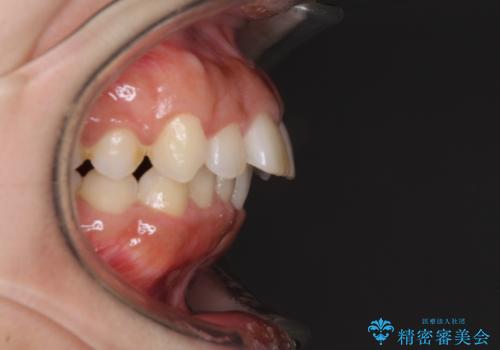

上下顎ともに前突しており、特に上顎は著しい突出感でした。

また、下顎歯列には左右差があり、非対称な抜歯が必要と判断されたため、治療は困難なものとなりました。

それでも根気強く通院してくださり、横からの顔貌の印象が大きく改善され、スムーズに口が閉じられるようになりました。